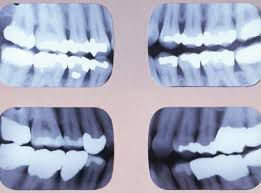

Bitewing X-rays show details of the upper and lower teeth in one area of the mouth. Each bitewing shows a tooth from its crown (the exposed surface) to the level of the supporting bone. Bitewing X-rays detect decay between teeth and changes in the thickness of bone caused by gum disease.